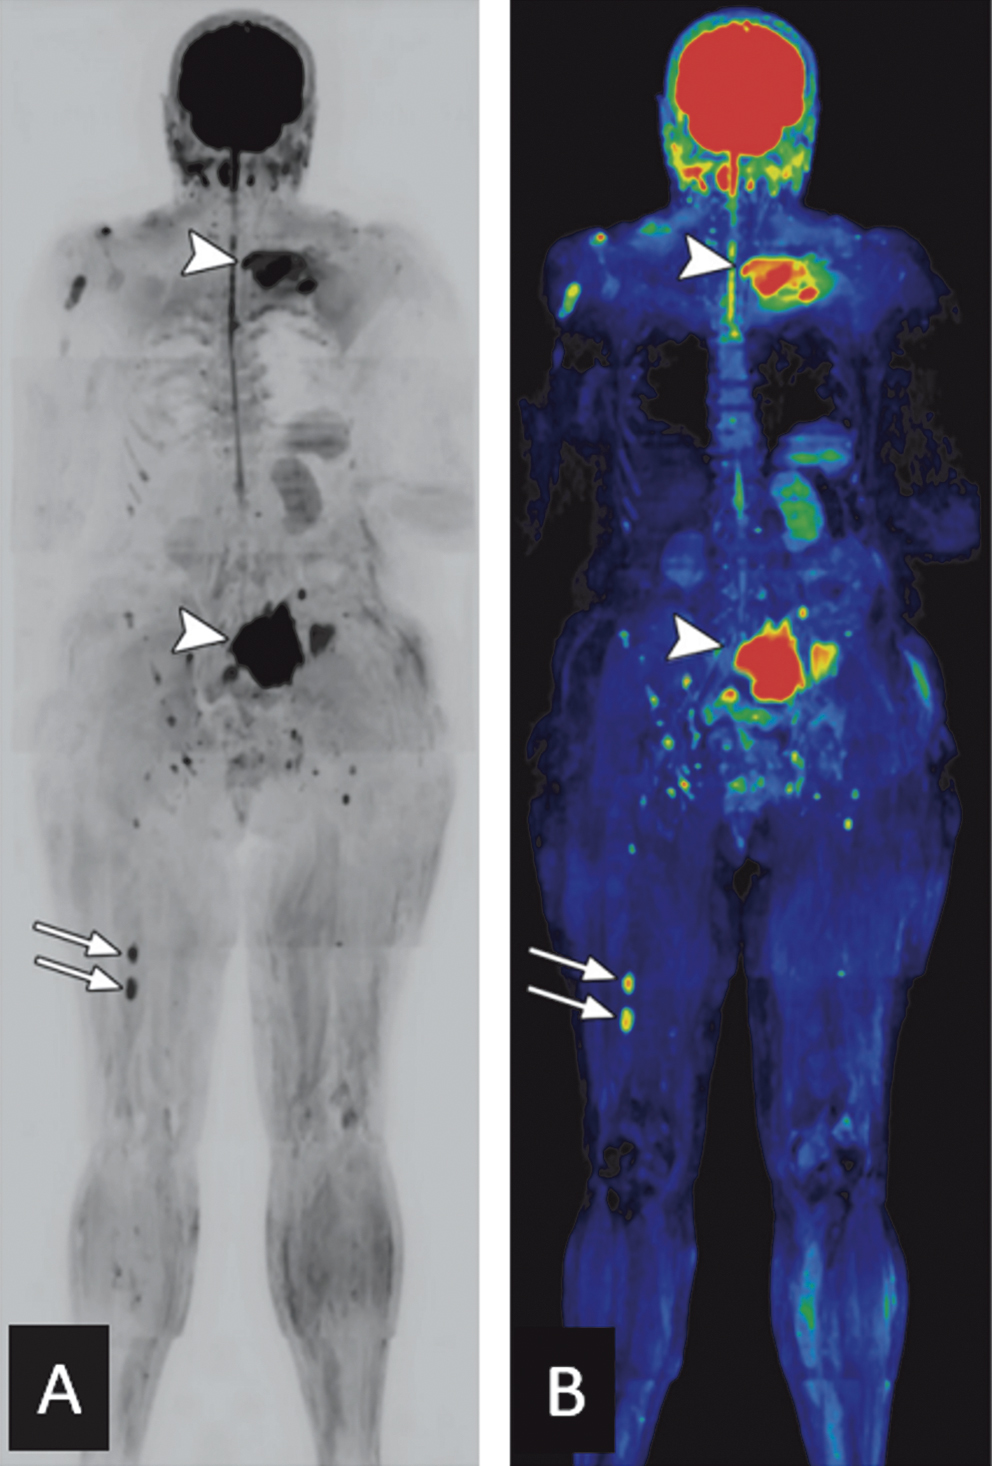

Na avaliação do paciente com DWI, podemos igualmente lançar mão do uso de inversão da escala de cinza com projeção de intensidade máxima (MIP), resultando em maior conspicuidade das lesões (figura 1A). A reformatação das imagens de difusão coloridas também pode ser útil, especialmente aos clínicos, para uma melhor compreensão da carga tumoral (figura 1B).

Figura 1. Achados em homem de 62 anos com dor nas costas, anemia e nódulo palpável na clavícula esquerda. Imagens de difusão coronal com escala de cinza invertida (A) e com reformação colorida (B) evidenciam pequenas lesões no fêmur direito (setas) e maiores lesões na clavícula e asa sacral esquerdas (pontas de setas), demonstrando também ruptura cortical e extensão extramedular.